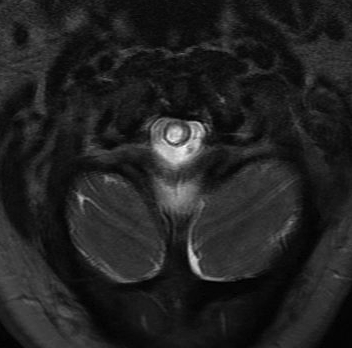

MRI

Most sensitive investigation

- main differential is oedema

- need T1 image

Look for obstructions

- ACM

- spinal cord tumours